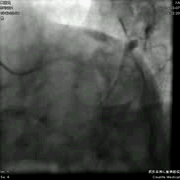

右冠造影: 右冠中段弥漫性狭窄,程度70%,PL远段狭窄90%。可见向左冠脉提供侧支循环。

![]()